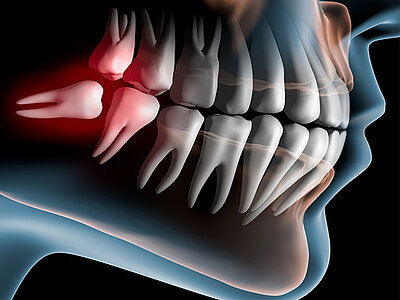

weisheitszahnentfernung

Ein routinemäßiger Eingriff, bei dem wir impaktierte oder problematische Weisheitszähne entfernen, um Problemen vorzubeugen.